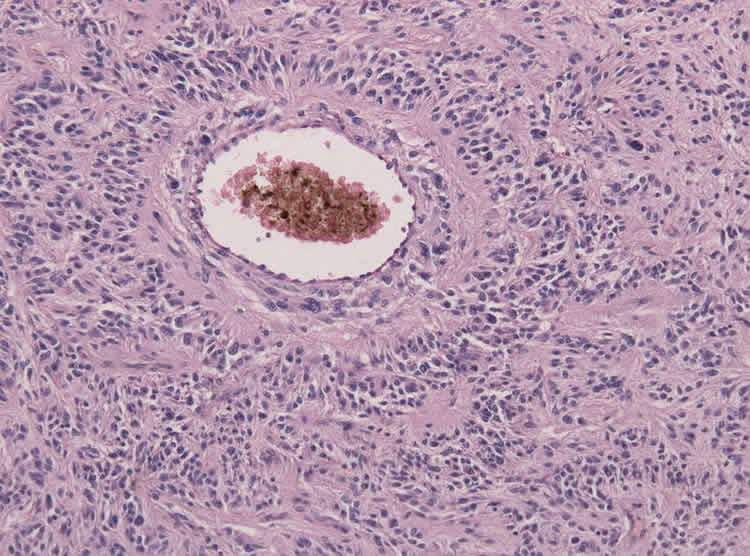

This image is a biopsy specimen of a Glioblastoma showing angiocentric growth reminiscent of ependymal neoplasms (HE stain).

Next-generation genome sequencing is allowing researchers to find increasingly more markers for a variety of diseases, including cancer and autism. This image is for illustrative purposes only and shows a biopsy specimen of a Glioblastoma showing angiocentric growth reminiscent of ependymal neoplasms (HE stain). Credit Jensflorian.